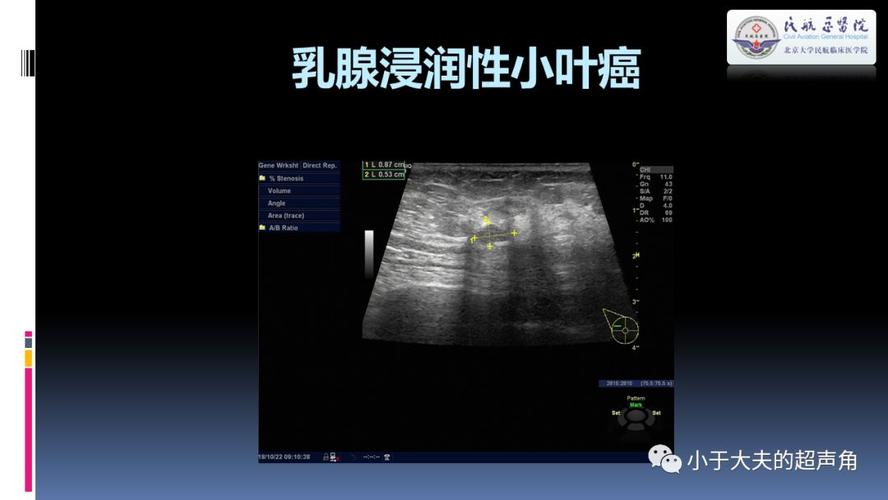

超声乳腺疾病欣赏

汇总史上最详细乳腺恶性肿瘤的超声诊断有图有真相

乳腺癌典型声像图 - 超声医学讨论版 - 爱爱医医学论坛

浸润性乳腺癌图片

浸润性乳腺癌